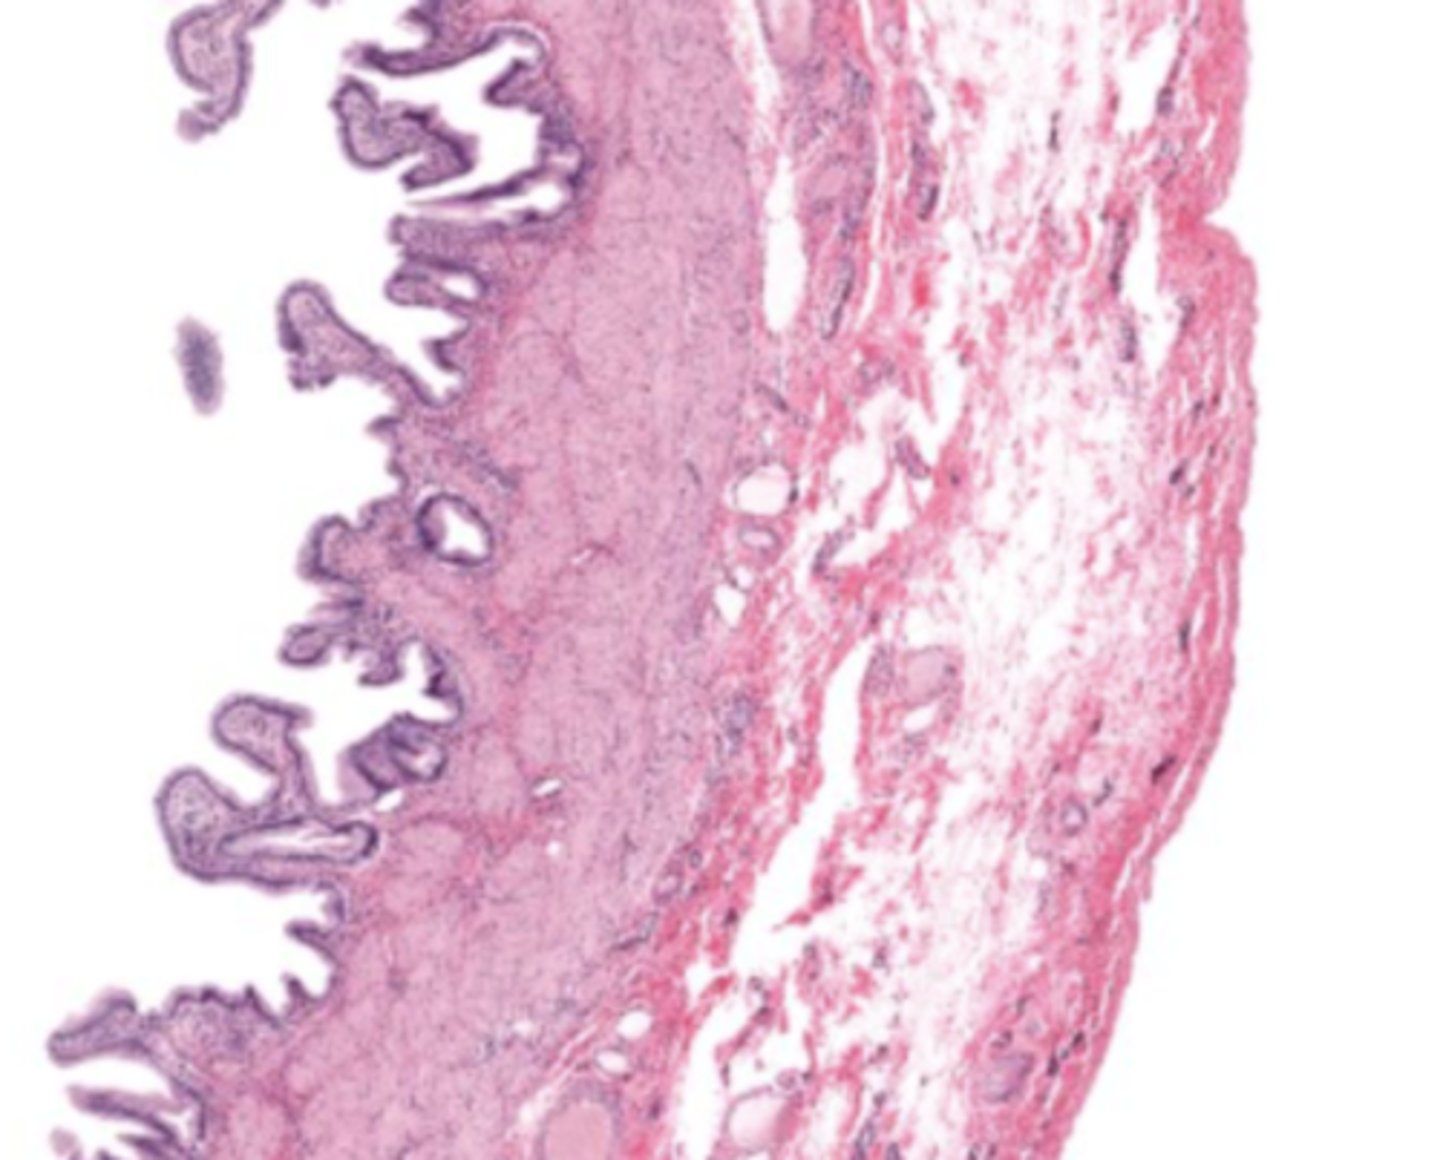

gallbladder (histology)

gallbladder

this tissue's wall structures/layers are different than the rest of the organs

simple columnar epithelium

what kind of epithelium lines the mucosa of the gallbladder

lumen (gallbladder)

mucosa (gallbladder)

mucosal epithelium (gallbladder)

lamina propria (gallbladder)

muscularis mucosa and submucosa

gallbladder tissue does not have _______ and ______

muscularis externa (gallbladder)

serosa/adventitia (gallbladder)